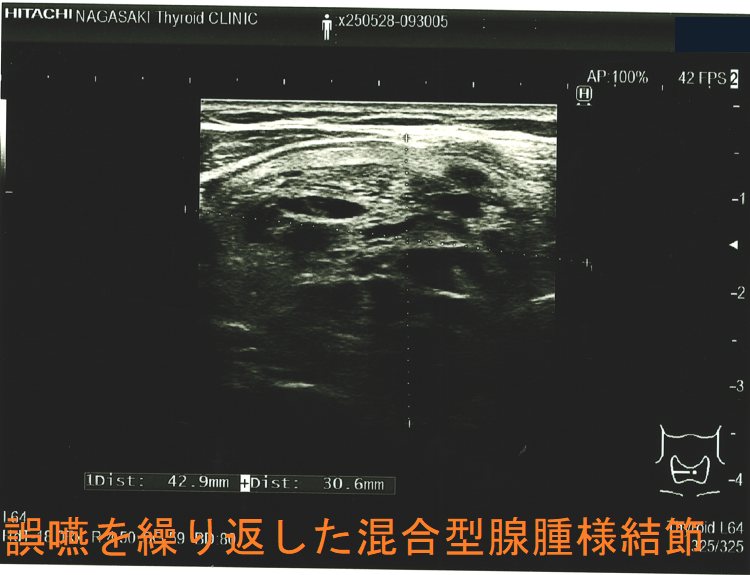

誤嚥を繰り返した混合型腺腫様結節